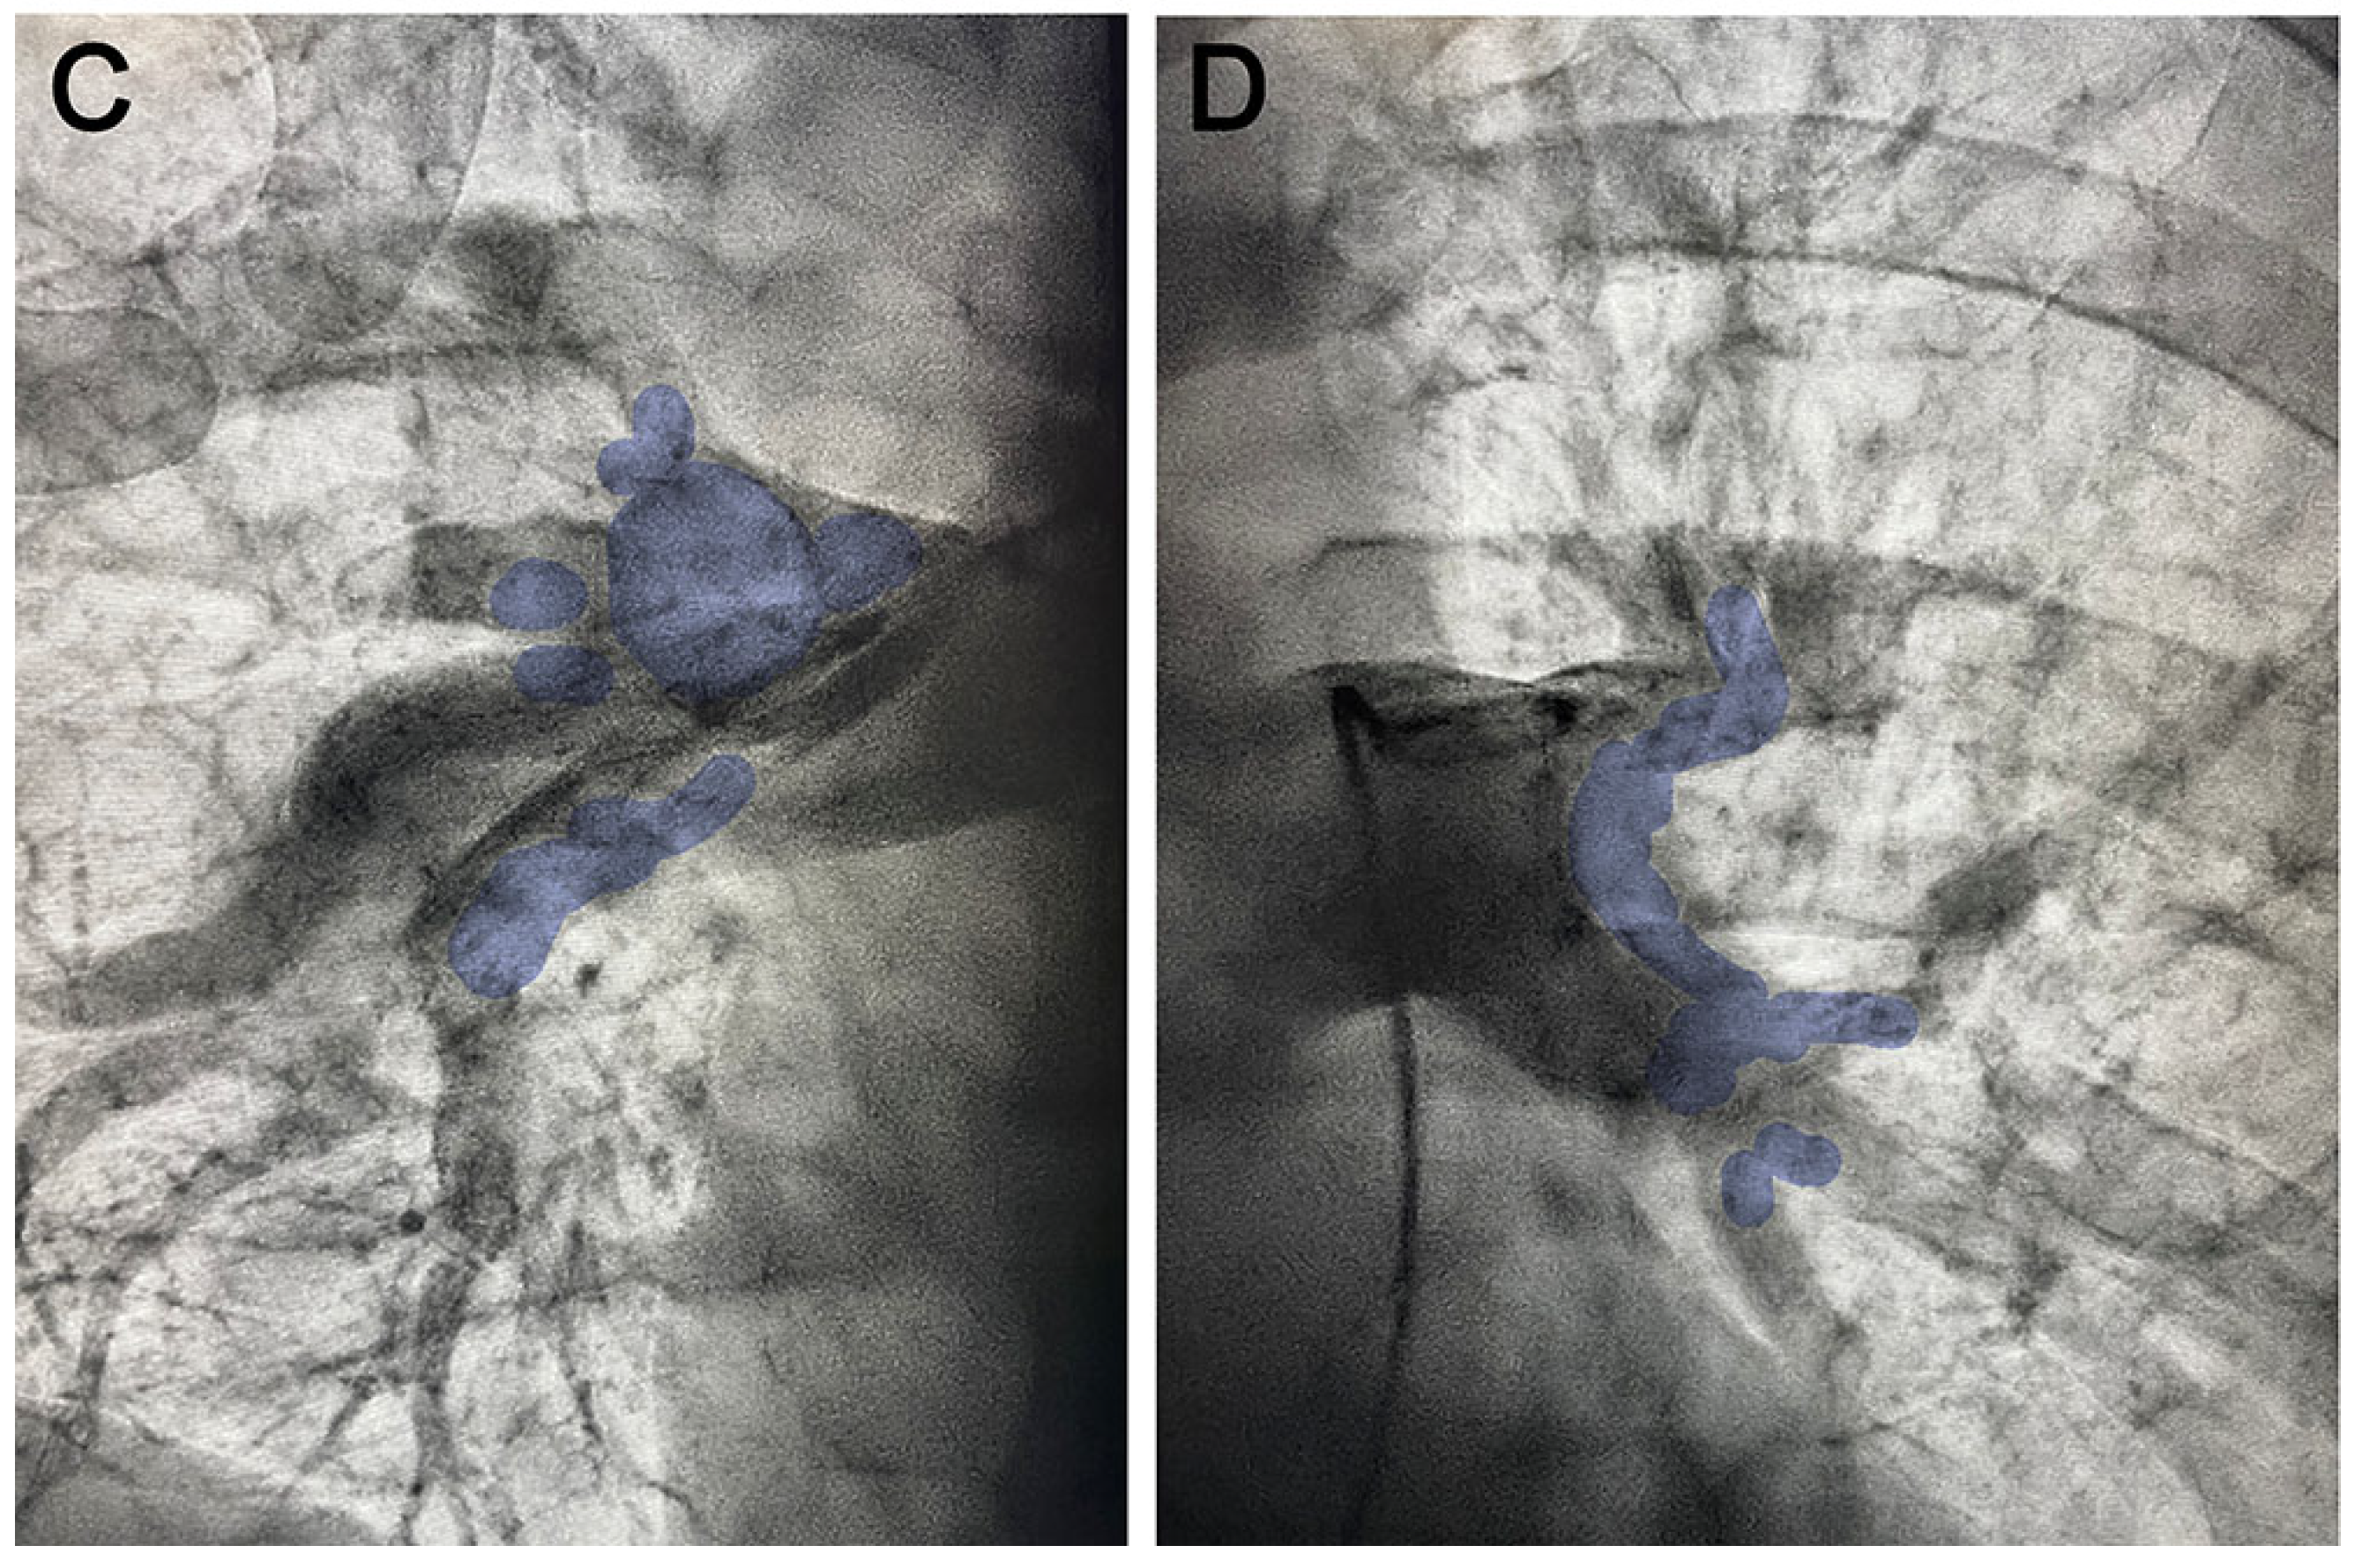

2. Case Report